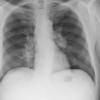

Lymphoma -Mediastinal and left axillary nodes

Date: 04/01/2014

Views: 3006